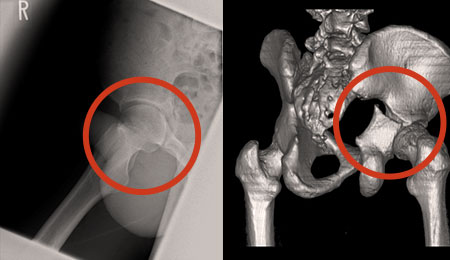

↑骨盤を激しく骨折した当時の写真↑

約10年前の交通事故で骨盤を激しく骨折し、その後遺症にも悩んできましたが、織田先生の施術を数回受けただけで激しかった痙攣も膝の痛みもなくなり、本当に驚きました!